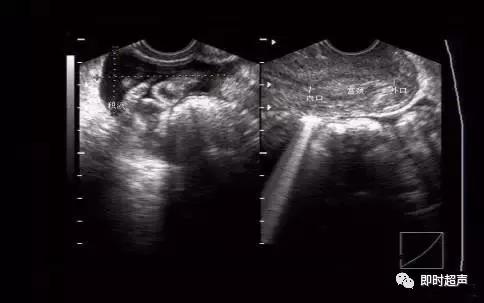

炎性积液和血性积液比较。另一声像图可见清晰宫颈管及宫颈内外口。

炎性液体内可见肠管飘动。血性液体内见较密集点状稍强回声。